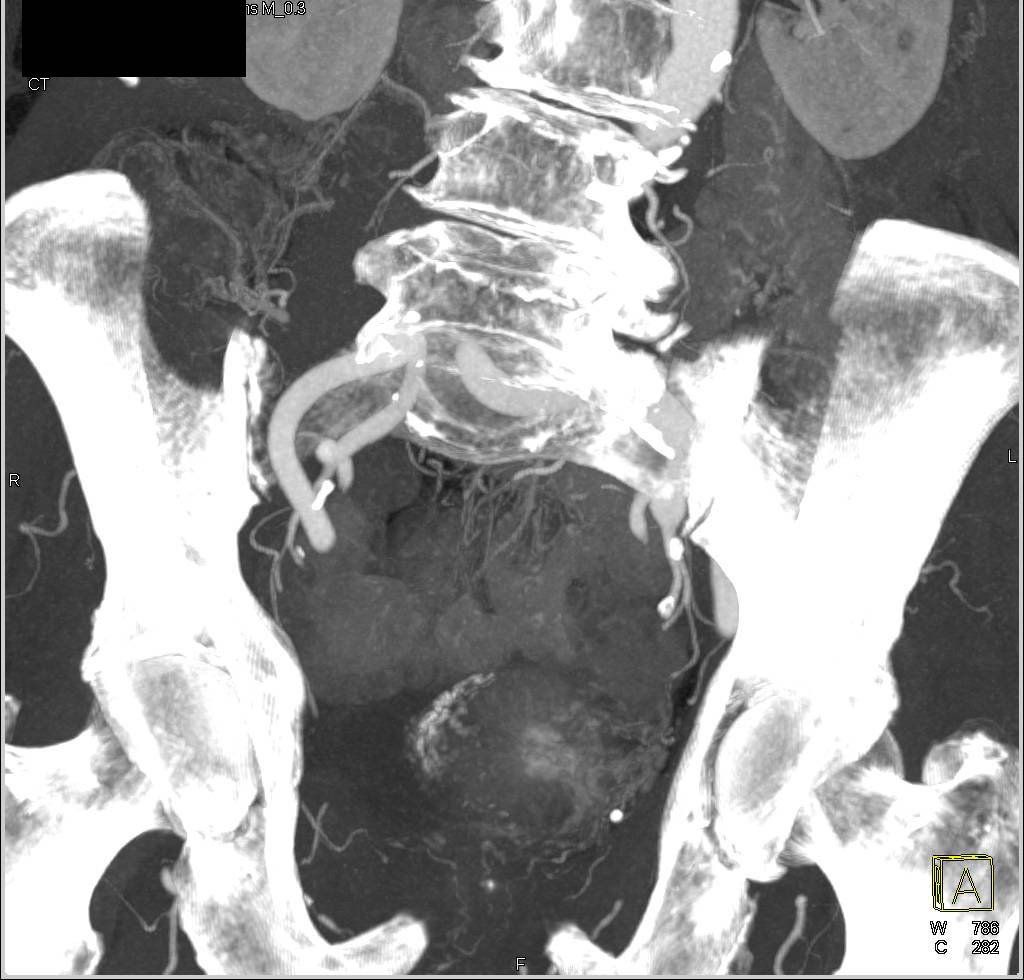

Primjer ispitivanja hematurije CT urografijom kroz slučajeve!

Slučaj 1. Karcinom urotelnih ćelija.

Slučaj 2. Karcinom mokraćne bešike.

Slučaj 3. Kamenci u bubrezima